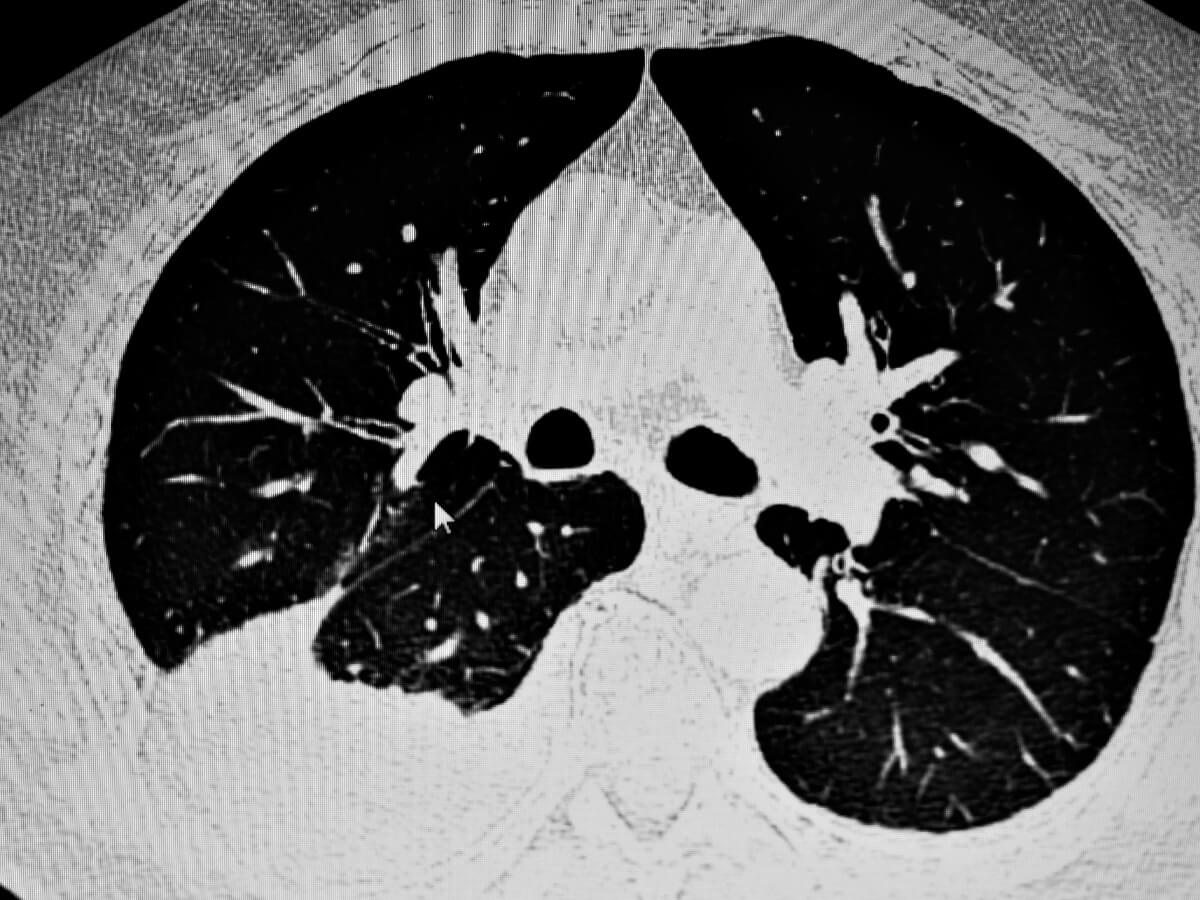

Når der først er mistanke om åndedrætsbesvær, bruges røntgenstråler normalt til direkte at observere dyrets medicinske tilstand. Ultralyd kan være nyttige, især når væskemængden akkumuleret i pleurahulen er meget lav.